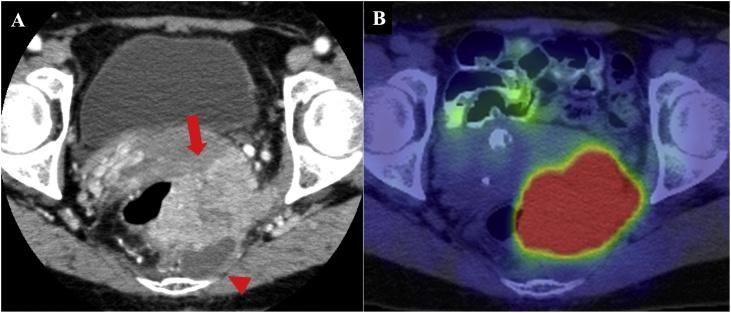

A 59-year-old woman complained of tenesmus and discomfort in the buttocks. Computed tomography revealed a 50-mm well-defined cystic mass in the presacrum and a 70-mm solid mass extending from the cyst into the rectum, vagina, and left sciatic spine. On T1-weighted magnetic resonance images, the cyst was unilocular and the mass was marginated with low intensity. On T2-weighted images, the mass had high intensity. A malignant presacral developmental cyst was diagnosed, without obvious metastasis. Using abdominal and parasacral approaches, Hartmann's operation was performed with multiorgan resection, including the sacrum, coccyx, left sciatic spine, internal obturator muscle, rectum, and uterine appendage. Histopathology of the excised specimen revealed a squamous cell carcinoma originating from the presacral epidermoid cyst.

Although further research is required, presacral epidermoid cysts are extremely rare and may be malignant. Thorough preoperative image evaluation is crucial for complete resection.